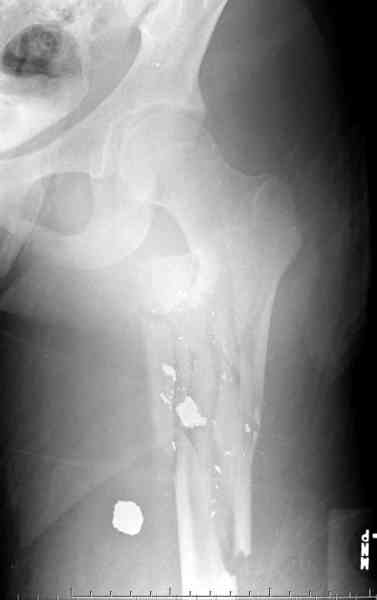

Богатый "урожай". Тяжелое дежурство..

3-й случай самый тяжелый и неоднозначный. Что с ранами? общим состоянием?

Молодой, с общим состоянием без проблем. Больной соперирован в день поступления и через два дня после операции выписан, так что не успел развиться гной.

Перелом низкоскоростным оружием, типа пистолетного, так что не стали гоняться за пулевыми фрагментами. С нервом пока подождем, иногда нерв восстанавливается если не прямое попадание в нерв, а "сотрясение" (shock wave injury).

Из всех типов фиксации взяли малоинвазивную технику мостовидной пластиной, использовали Locking проксимальную Synthes пластину.